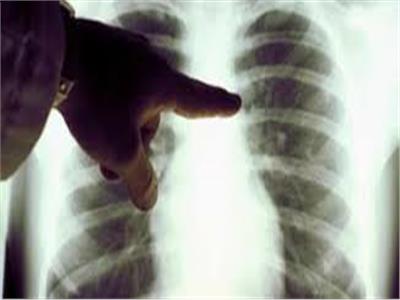

- وأيضًا تصوير الصدر بالأشعة السينية؛ لتحديد مدى تراكم السوائل في الرئة.